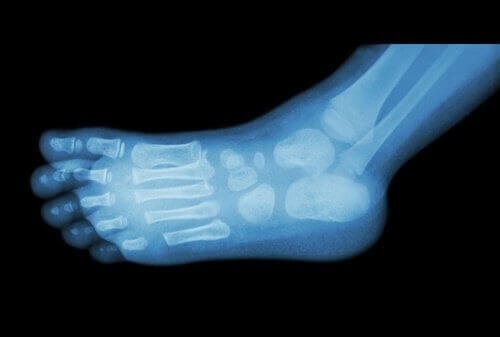

Hælspore kan diagnosticeres ved hjælp af en simpel røntgenundersøgelse.